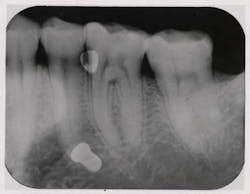

Fig. 1c — Bitewing taken by hygienist three weeks after returning from an outside office reveals nonseated implant abutments on teeth Nos. 18 and 19. Patient complained of too many radiographs being taken.